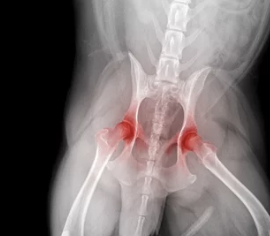

강아지 관절염은 관절에 염증이 생겨 통증과 움직임 제한을 유발하는 질환입니다. 특히 나이가 들수록 발병 가능성이 높아지며, 소형견보다는 대형견에게 더 흔히 발생합니다.

- 유전적 요인 (고관절 이형성증, 슬개골 탈구 등)

- 고관절 이형성증의 경우 교정 수술을 시행